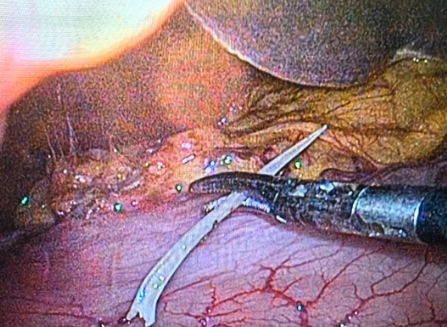

主刀医生柳承业深耕微创外科多年,技术娴熟、经验老道,带领手术团队从容有序、精准高效地实施手术。麻醉生效后,患者取仰卧位,手术团队凭借精准的解剖定位能力和娴熟的操作技巧,于脐上精准置入气腹针,成功建立人工气腹并轻柔提起腹壁,再于脐孔处置入10mm穿刺套管,顺利插入高清腹腔镜。借助腹腔镜的实时高清视野,手术团队对腹腔内情况进行全面、细致的探查,精准掌握腹腔内粘连情况及异物位置,为后续手术操作筑牢基础。

在腹腔镜的精准引导下,手术团队先后于患者左侧、右侧腹直肌外侧缘各置入1个5mm穿刺套管,搭建高效、微创的手术操作通道,最大限度减少患者创伤。探查中,手术团队凭借敏锐的临床洞察力,快速发现患者胃窦部与肝脏脏面存在明显粘连,为避免损伤肝脏、血管等周围重要脏器,主刀医生手法轻柔、精准细致地松解粘连组织,全程动作稳健、精准可控,最终清晰暴露病灶——一枚尖锐鱼刺从胃窦部刺出,尖端已深深没入肝脏脏面。因为鱼刺扎入胃壁已经一月,随着胃的蠕动刺穿胃壁,进入腹腔,刺入肝脏,刺伤胃黏膜处已经愈合,鱼刺根部较粗的位置卡在胃壁肌层。这也是胃镜没有探查到鱼刺的原因所在。

面对危急病灶,主刀医生沉着冷静,依托精湛的腹腔镜操作技术,稳稳操控手术器械夹住鱼刺,精准把控力道与时机,缓慢、轻柔地将异物完整取出,全程杜绝了鱼刺断裂残留腹腔、造成二次损伤,同时成功规避了肝脏及周围血管损伤的风险。经测量,这枚引发危机的鱼刺,长度竟达4cm!